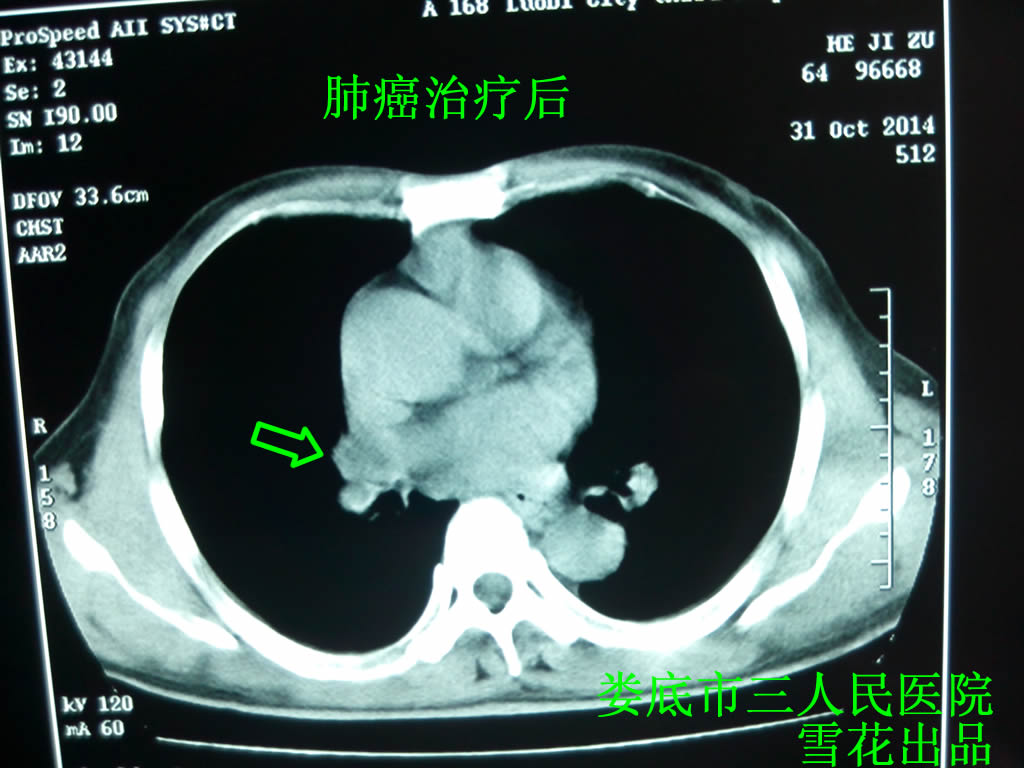

口服3剂后痰中带血明显好转,顺利完成第一周期化疗,坚持口服上方,痰中带血逐渐消失,2014.10.10行第2周期化疗(方案同前),患者无明显化疗反应,调整中药,去陈皮,加蜈蚣2条,坚持口服中药。2014.10.31来院复查,患者诉无胸痛咯血,咳嗽气促明显好转;患者女儿诉其父在家小跑一段后仍能面不改色。查肺部CT示:右肺门区肿块及右中肺阻塞性炎症较前明显好转,左肺上叶小结节稍高密度灶基本吸收(见图二)。复查B超示肾上腺肿块消失,肝脏多发占位性病变较前无明显变化。再次追问病史,患者女儿诉其父曾于2006年查出有多发性肝血管瘤病史,所以雪花认为患者肝脏多发占位性病变不一定是转移瘤,继续治疗,定期复查。